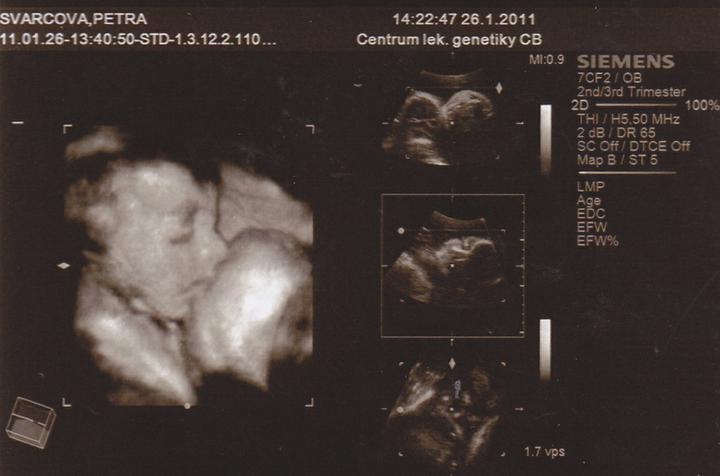

26.1.Jedu do Českých Budějovic na 4D ultrazvuk.Už se nemůžu dočkat.

Včera jsem Byla v Českých Budějovicíh.Jedno mimi váží 267g, a druhé váží 314g.A jsou to kluci.